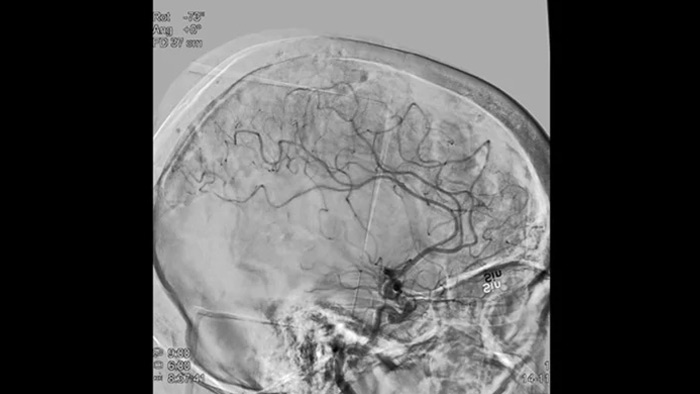

SmartCT Vaso IV

Comprobar la ubicación y la longitud del coágulo

SmartCT Vaso permite la visualización más allá del coágulo con imágenes periprocedimiento de las caras distales de los vasos en el accidente cerebrovascular isquémico. SmartCT Vaso es una técnica de adquisición basada en una TC de haz cónico y una inyección de contraste intrarterial. Permite la visualización más allá del coágulo con imágenes periprocedimiento de las caras distales de los vasos en el accidente cerebrovascular isquémico. Mediante el llenado retrógrado, se ven las estructuras de los vasos antes y después del coágulo. SmartCT Vaso 3D Roadmap puede utilizarse para visualizar los dispositivos de recuperación de coágulos.